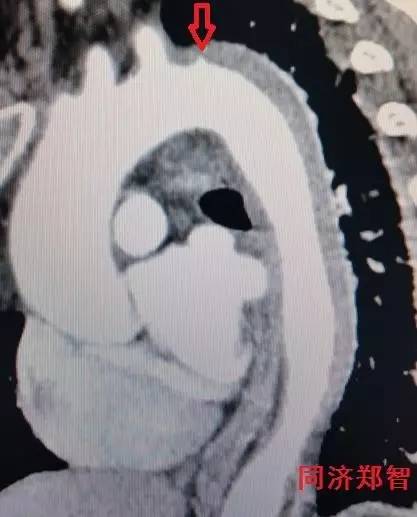

CTA轴位片显示主动脉弓穿透性溃疡(图11)。

图11